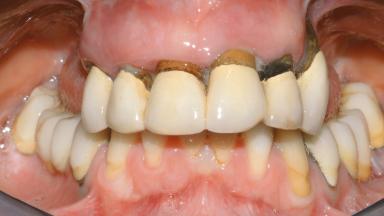

Conventional Loading of Eight Implants in the Maxilla and Final Restoration with a Full-Arch Gold-Ceramic FDP

A 35-year-old Caucasian female presenting with advanced periodontal disease involving both the maxillary and the mandibular dentition was referred for evaluation. The patient, a non-smoker in good general health, requested treatment for recurrent periodontal abscesses, tooth mobility, and discomfort during chewing, as well as restoration of her missing teeth with a fixed prosthesis to improve mastication and esthetics. All residual maxillary teeth exhibited plaque deposits, deep pockets, bleeding on probing, and class III mobility and were evaluated as hopeless. All residual mandibular teeth except tooth 37 could be maintained after periodontal therapy.

Prosthesis Type FDP

Defining Characteristics Fully edentulous upper jaw to be rehabilitated with an implant-borne fixed dental prosthesis